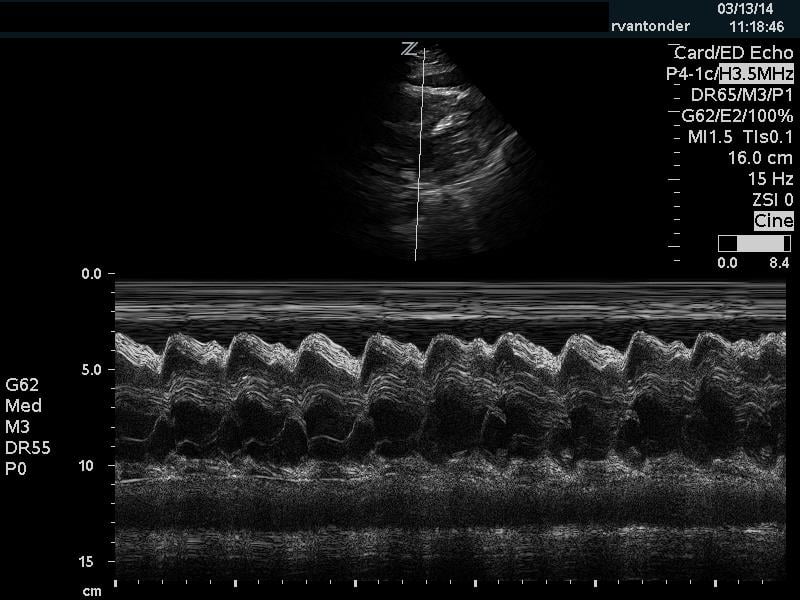

The cardiac component is essential to evaluation of a hypotensive patient as it can provide valuable information about cardiac physiology and etiology of shock. The goal of the cardiac portion of the examination is to classify presence or absence of pericardial effusion, pericardial tamponade, evaluate left and right ventricular contractility and chamber size and thus link these findings to the etiology of shock. Pericardial effusion with tamponade may be identified as a cause of obstructive shock. As fluid and pressure in the pericardial sac increases, early diastolic collapse of the right ventricular free wall is seen. (Video 1) This can be assessed visually in the parasternal long view by placing an M-mode line through the right ventricle (RV) and left ventricle (LV), including the interventricular septum and anterior leaflet of the mitral valve. (Figure 3) This allows for easy identification of right ventricular diastolic collapse, which is indicative of tamponade physiology.

Figure 3. Right ventricular diastolic collapse viewed in M-mode. Note motion of mitral valve leaflet, in the mid-field. Valve opening indicates diastole, which can then be compared to the collapse of the right ventricle in the near field.